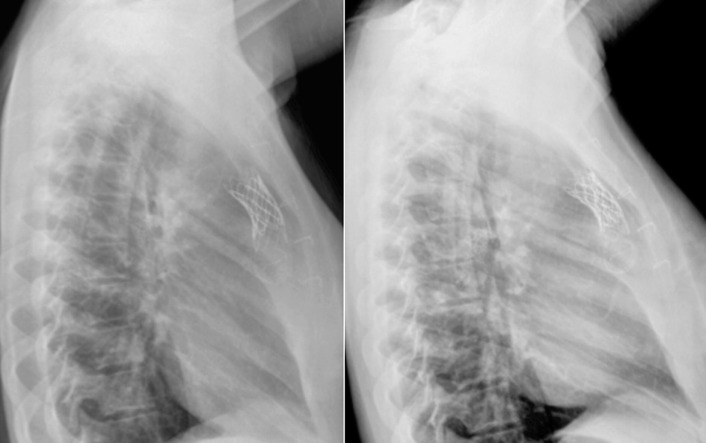

Percutaneously inserted heart valves are evident on chest radiography.

The position of percutaneous heart valves can be visualized by chest radiography, as can some complications and dysfunction.

Thoracic aortic stenting/endografting is increasingly performed as treatment of coarctation of the aorta, aneurysm of the thoracic aorta, false aneurysm of the thoracic aorta, penetrating ulcers, and dissections ( Table 13-2 ). Thoracic aortic stenting may employ either uncovered or (ePTFE)-covered stents, depending on the nature of the lesion and the desired intervention. The supportive wire network of aortic stents is readily visible on chest radiography. FLOAT NOT FOUND FLOAT NOT FOUND FLOAT NOT FOUND FLOAT NOT FOUND FLOAT NOT FOUND FLOAT NOT FOUND FLOAT NOT FOUND FLOAT NOT FOUND FLOAT NOT FOUND FLOAT NOT FOUND